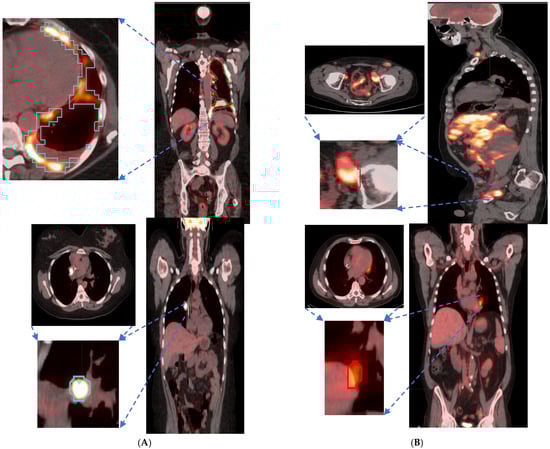

We found that the shape- and size-based radiomic PC metrics on extranodal cohort were significant (p < 0.05) for OS and PFS, in PET images (see Table 4). We illustrate patients’ image scans with high and low shape metrics (see Figure 2). We used the Cox-regression model to assess patients’ proportional hazard (HR) to treatment outcome, measured by survival (OS/PFS). We first evaluated the clinical metric, MTV, to outcome, and found an HR of 3.885 and 3.64 for nodal (lymphatic) and extra-nodal (non-lymphatic) cohorts. The c-index is 0.67/0.65 for nodal (lymphatic)/extra-nodal (non-lymphatic) cohorts (see Table 5). We found that size and shape PCs on extra nodal CT and PET radiomic PCs were significant and showed higher risk for adverse outcomes (c-index 0.59 to 0.6 for shape and 0.61 to 0.6 for size, in OS/PFS, respectively). Texture-based radiomic PCs on extranodal CT show significance (c-index 0.61/0.6 for OS) (see Table 5).

Figure 2.

Patient scans showed representative slices in the fused image (CT/PET) with a pointing arrow towards lesions with significant uptake. Representative patients (Lung and Abdominal) image slice for (A) High shape metric and (B) Low shape metric.